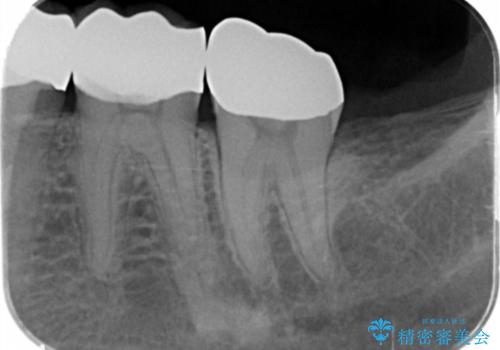

適合の良いゴールドクラウンが入りました。

患者様に満足して頂けました。

ゴールドは適合が良く、割れる心配もありません。

また、虫歯になるリスクも銀歯と比べて低くなります。